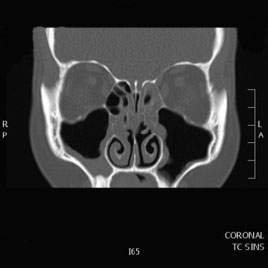

Tomografía computarizada Senos y Estructuras Nasales

Se utiliza para el estudio de los senos paranasales y diferentes estructuras de la fosa nasal.

Ejemplos